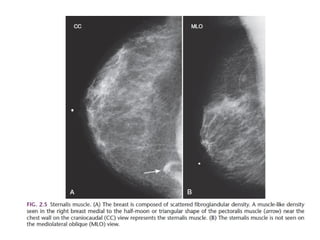

Breast imaging power point